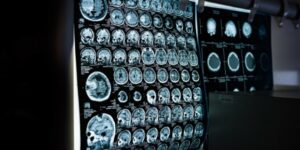

Analysis of biomedical images is a hot topic related to computer diagnostics. Mathematical methods and medical image analysis software are already helping to significantly simplify and speed up the diagnosis of diseases, especially in the early stages.

Custom medical image analysis solutions for radiology